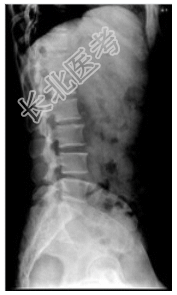

- [材料题] 患者,女性,50岁。腰痛1个月。查体:心、肺(-),腹平软,无压痛,腰部叩击痛。行腰椎正侧位检查。

- 简答题1、患者的诊断及依据是什么?

- 简答题2、鉴别诊断有哪些?